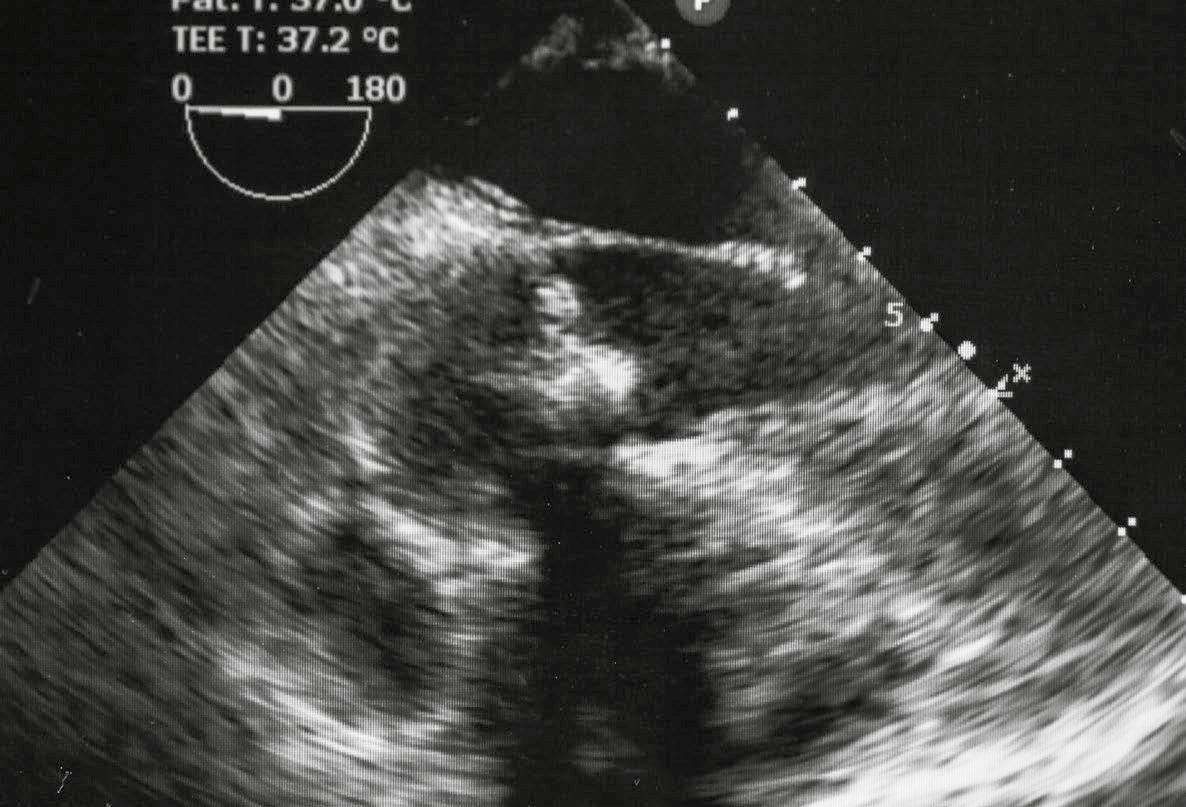

REEMPLAZO TRANSCATÉTER DE VÁLVULA AÓRTICA

UNA ALTERNATIVA QUE OTORGA AÑOS Y CALIDAD DE VIDA EN PUERTO RICO

DESDE HACE SIETE AÑOS, LOS BORICUAS CUENTAN CON UNA ALTERNATIVA QUE HA SALVADO MUCHAS VIDAS, MEJORANDO LA CALIDAD DE VIDA DE PACIENTES CON AFECCIONES CARDÍACAS.

Conversamos con el experto, buscando aclarar los detalles sobre el reemplazo de la válvula aórtica, y un procedimiento revolucionario que hace parte del arsenal con el que cuentan los profesionales y pacientes en Puerto Rico, nos referimos puntualmente al ‘reemplazo transcatéter’.

Según explica Martínez, el procedimiento es relativamente nuevo en la isla. Desde el 2016 se empezó a prestar esta alternativa a los pacientes y según estima el especialista, anteriormente, cerca de un 30 - 40 por ciento de los pacientes fallecían porque no podían beneficiarse de la intervención.

Como director del Departamento, la data que revela es alentadora, dejando claro que cerca de 120 pacientes, desde el 2020, se han beneficiado del reemplazo de válvula percutáneo, con una sobrevida muy buena.

Por otra parte, el reemplazo transcatéter de la válvula aórtica, explica Martínez que brinda grandes beneficios y uno de ellos es la recuperación: “la salida es otorgada a las 24 horas siguientes”. El paciente puede empezar su recuperación en casa por ser un procedimiento mínimamente invasivo, aunque de presentarse alguna complicación, debe permanecer hospitalizado, pero “las complicaciones tienden a ser mucho menores”.